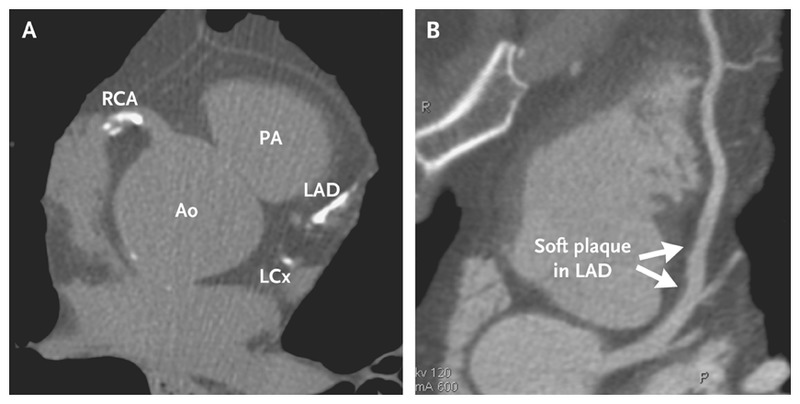

1- برای بررسی تنگی عروق کرونر: تنگی عروق قلبی و نرسیدن خون به آنها یا " ایسکمی" زمانی ایجاد می شود که دیواره عروق کرونر (رگ های تغذیه کننده قلب) در اثر رسوب چربی شروع به ضخیم شدن ، سفت شدن و تجمع پلاک می کنند ، پدیده ای که به "آتروسکلروزیس" معروف است. در طول زمان تنگی ایجاد شده پیشرفت کرده و در نهایت می تواند به "سکته قلبی" و "سکته مغزی" منجر شود.